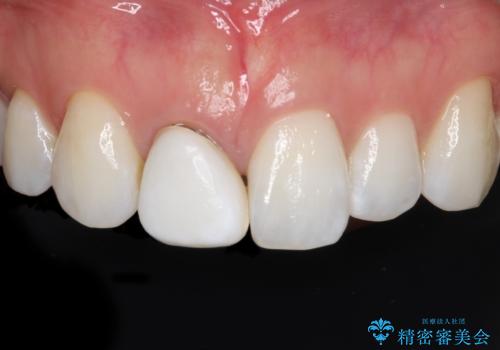

オールセラミッククラウンは、金属を使用しないため、自然光の下でも透過性が高く、天然歯と見分けがつかないほど美しい仕上がりが得られる素材です。また、金属アレルギーの心配がなく、長期間使用しても歯ぐきへの影響が少ないという利点があります。